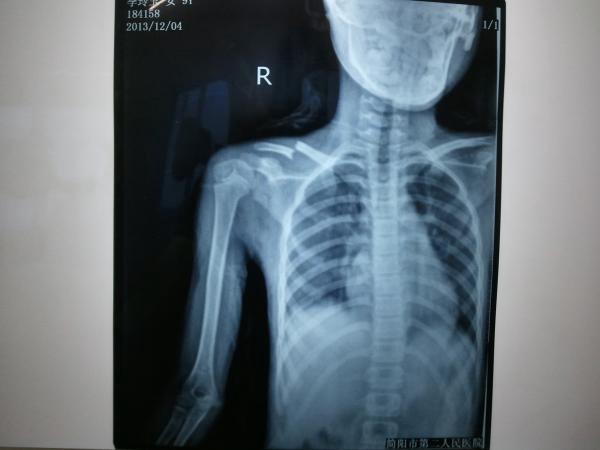

九岁儿童锁骨骨折,闭合复位经皮内固定。

患儿九岁,跌倒伤右肩入院。查:右肩下垂,头偏向右侧,下颌转向左侧,左手托右肘。锁骨上凹饱满,压痛,骨擦感。DR:右锁骨骨折。入院完善检查,手法复位经皮內固定。